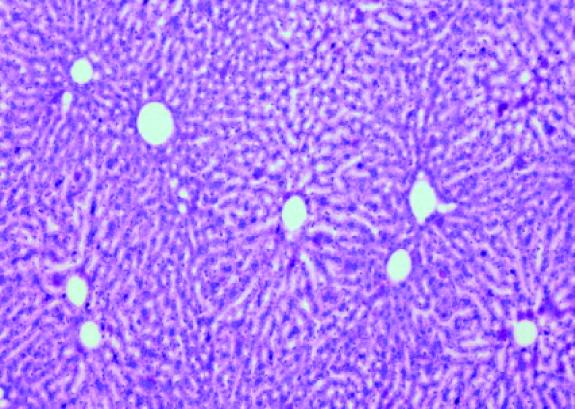

The liver stores excess glucose, sugar, in the form of glycogen--chains of glucose--, which is later released to cover body energy requirements. Diabetic patients do not accumulate glucose well in the liver and this is one of the reasons why they suffer from hyperglycemia, that is to say, their blood sugar levels are too high. A study headed by Joan J. Guinovart at the Institute for Research in Biomedicine (IRB Barcelona) demonstrates that high hepatic glucose stores in mice prevents weigh gain. The researchers observed that in spite of having free access to an appetizing diet, the animals' appetite was reduced. This is the first time that a link has been observed between the liver and appetite.

The researchers questioned why mice that accumulated most glycogen in the liver did not gain weight in spite of having access to an appetising diet. In addition to observing that these animals ate less, the scientists found that the brains of these animals showed scarce appetite-stimulating molecules but rather many appetite-suppressing ones.

The key to the liver-brain link is ATP, the molecule used by all living organisms to provide cells with energy and which is commonly altered in diabetes and obesity. "We have seen that high levels of hepatic glycogen, stable levels of ATP, and high levels of appetite-suppressing molecules in the mouse brain are perfectly correlated," explains López-Soldado.